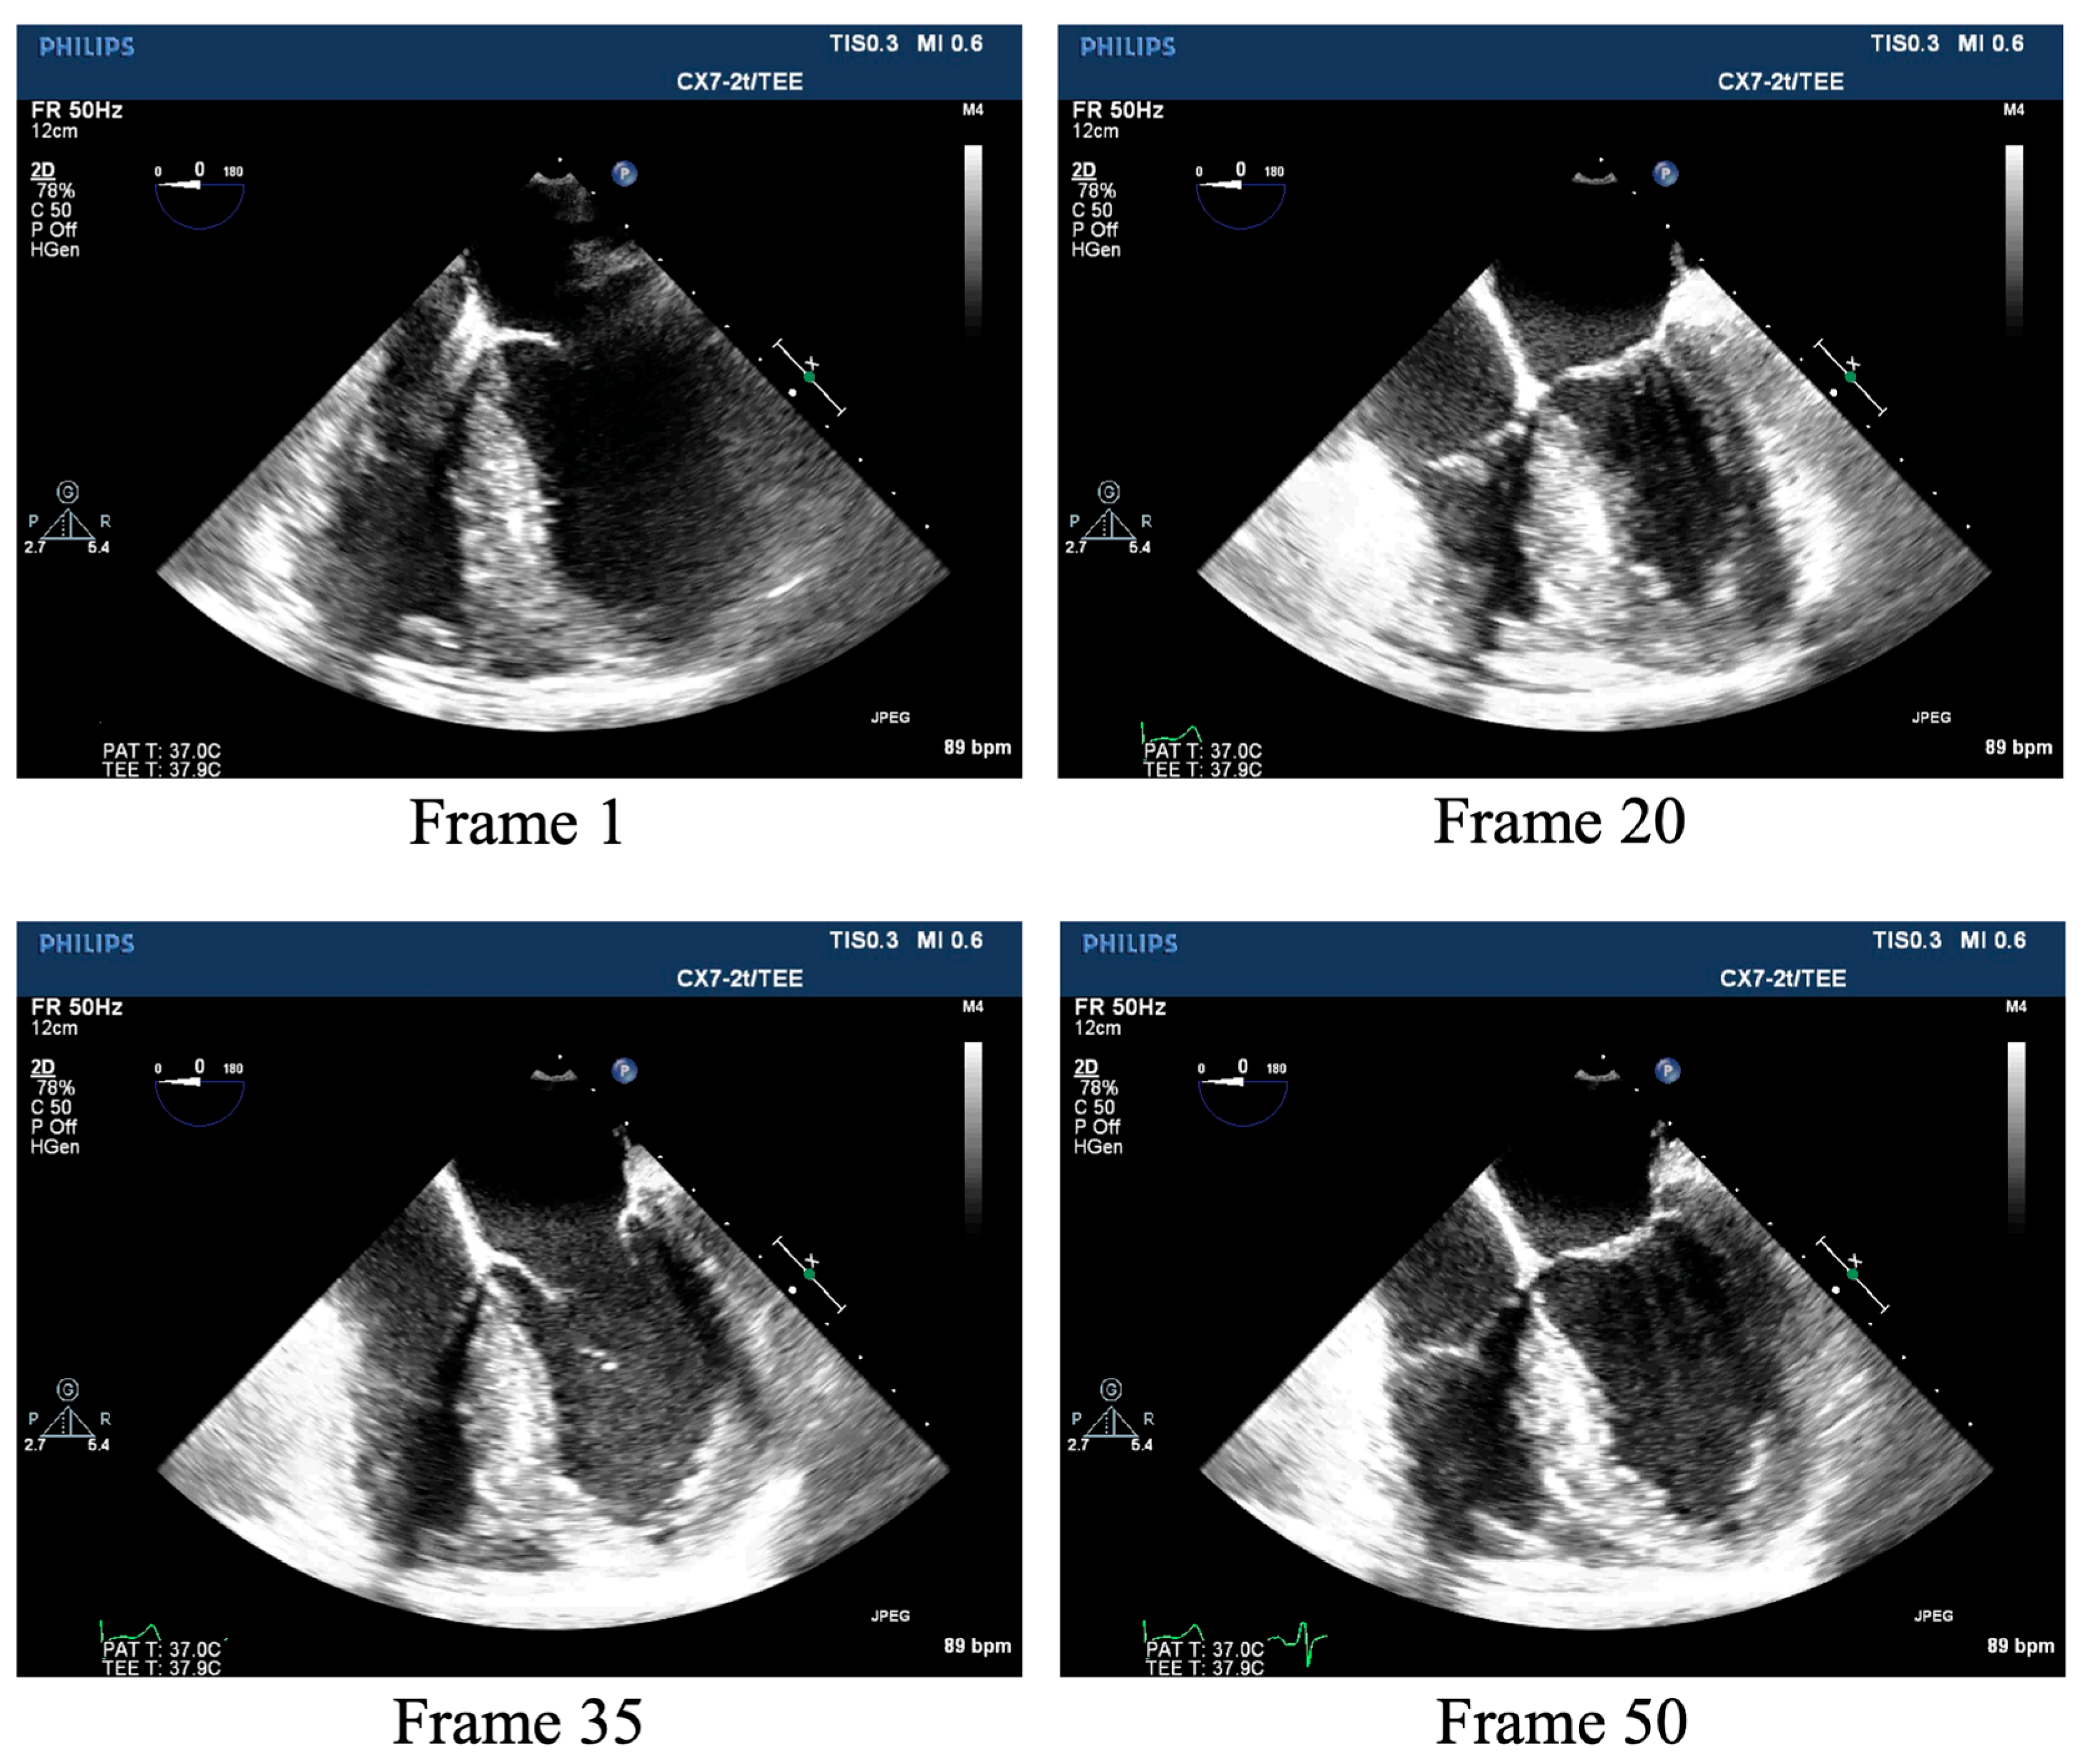

2.1. TEE Dataset

2.1.1. Data Collection